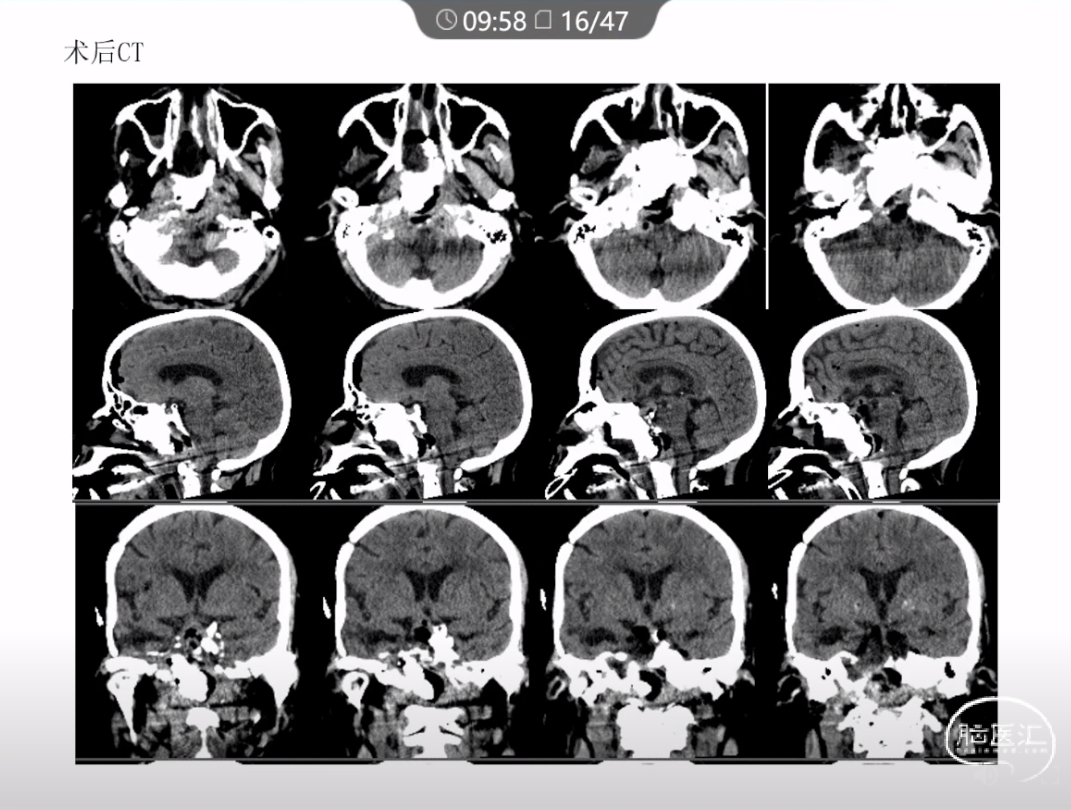

本文主要内容为:脊索瘤临床特点、治疗选择,以及多个手术病例。